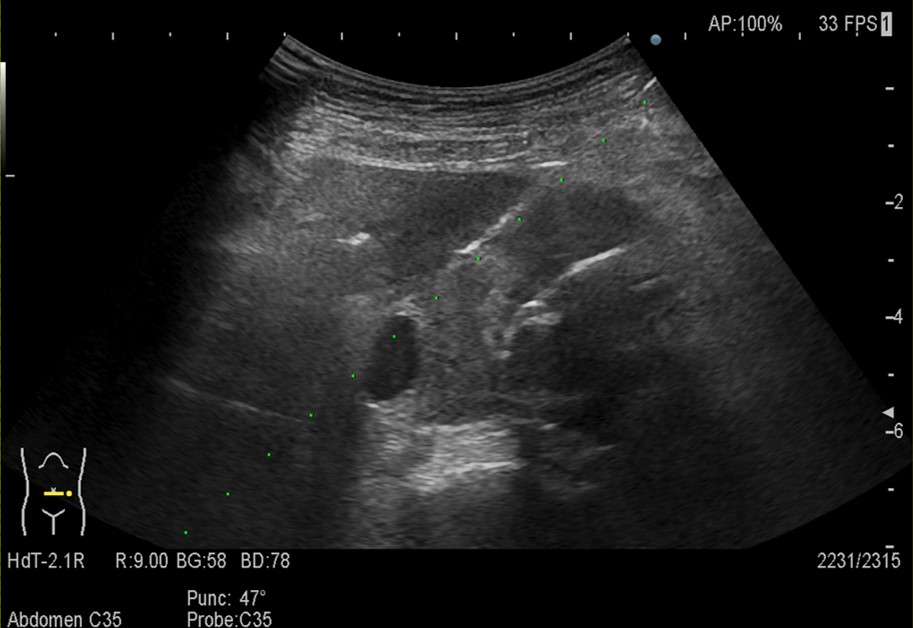

【超音波ガイド下針生検】

診断:ステントグラフト挿入術後に生じた大動脈原発肉腫(Aortic epithelioid angiosarcoma)および肺転移